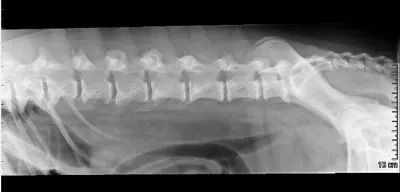

Lateral radiograph of a canine spine showing clear alignment of the vertebrae, with no signs of fractures or abnormalities. The surrounding soft tissue structures are also visible, providing context for the spinal anatomy.

Although bony proliferation of the facets is usually external to the vertebral canal, spinal stenosis leading to spinal cord compression is possible; however, more common conditions, such as disk herniation, should be ruled out in dogs with neurologic signs and spinal pain. Arthritis in the lumbosacral region can be associated with cauda equina syndrome.

Spondyloarthropathy is diagnosed radiographically by the presence of bony proliferation, sclerotic margins, and osteophytosis of the articular facets, and is not necessarily associated with ventral spondylosis deformans. Osteochondritis dissecans lesions or congenital hypoplasia of the articular facets (arrows) can also be seen in young dogs; although not commonly diagnosed, these findings (which can lead to spondyloarthropathy) may be underrecognized in patients that do not undergo advanced imaging studies. Myelography, computed tomography, or magnetic resonance imaging is indicated to determine if bony proliferation due to degenerative joint disease is causing spinal compression.